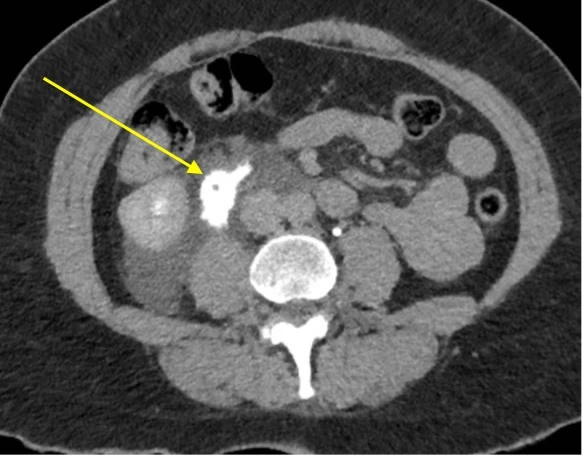

Cette image est celle d’un scanner abdominal en phase veineuse tardive, et montre une collection d’urine rétro-péritonéale (flèche). Il s’agit d’un urinome. Cette pathologie survient après une rupture urétérale, provoquant une fuite d’urine, qui se collecte et qui prend le contraste tardivement au CT.

• Le CT natif et l’ultrason : permettent de montrer une dilatation pyélocalicielle éventuelle, et la collection.

• Le CT injecté en phase tardive (réalisé dans un deuxième temps en cas d’insuffisance rénale aiguë !) : met en évidence le signe de la toile d’araignée (visualisation des septas périrénaux) et montre une extravasion de produit de contraste sur rupture du fornix (région pyélocalicielle), de la jonction pyélo-urétérale ou de l’uretère. Il a l’avantage, par rapport à l’ultrason, de confirmer l’origine et la localisation de la brèche.